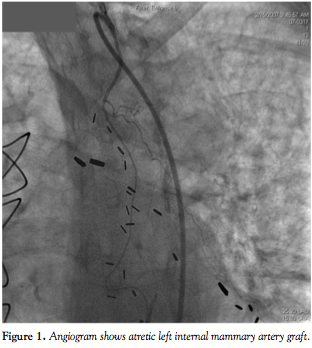

diaphoretic and hypotensive. Electrocardiography (ECG) showed atrial fibrillation with rapid ventricular response and ST elevation in leads V1–V2. Hemodynamic stabilization was achieved with amiodarone and digoxin. Emergency left-heart catheterization was performed and thrombus was noted at the site of the prior stent without flow in the distal vessel (Figure 2). The right coronary artery and LIMA graft, respectively, were not visualized, as they were known to be totally occluded and atretic.